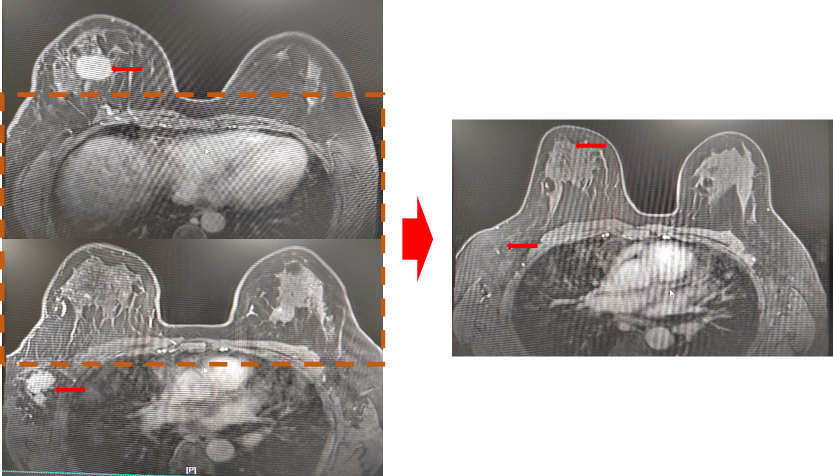

▌影像学评估(MRI):

图5. 基线与4周期治疗后MRI影像

该患者分别于2021-10-15、2021-11-5、2021-12-1、2021-12-22、2022-1-13、2022-2-8完成6周期新辅助化疗,方案:TCbHP,紫杉醇脂质体210mg+卡铂 0.6g+汉曲优(首次剂量 500mg,维持剂量380mg)+帕妥珠单抗(首次剂量 840mg,维持剂量420mg),该患者在完成第一周期新辅助化疗后,自觉肿块明显缩小,在行第3周期新辅助化疗入院后,予以完善乳腺MRI提示,乳腺肿物及腋窝淋巴结均明显缩小,查体几乎无法触及乳腺肿物及腋窝肿大淋巴结,继续完成6周期足量新辅助化疗后行乳腺癌改良根治术。